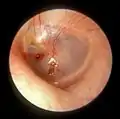

![]() Right eardrum as seen through a speculum | |

Right eardrum as seen through a speculum